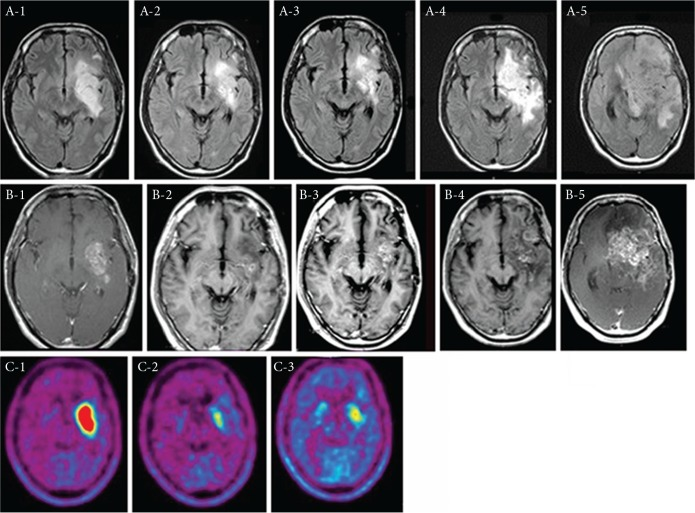

一名36岁男性,患有复发性间变性少星形细胞瘤。爱国军被列为二级。在接受BNCT和BV治疗之前,他抱怨说癫痫很难控制。治疗后,癫痫发作可以得到很好的控制,患者的核磁共振成像表现出改善。在BNCT之前、之后7个月和之后13个月,重复的双酚a正电子发射断层扫描分析分别得出了5.0、1.9和2.1的左/右比值,如所示图1。不幸的是,核磁共振成像恶化了图1A-4和B-4,患者在BNCT手术后38个月死于肿瘤进展。患者接受了55个疗程的BV。突出的AE是全身疲劳和蛋白尿(CTCAE 2级)